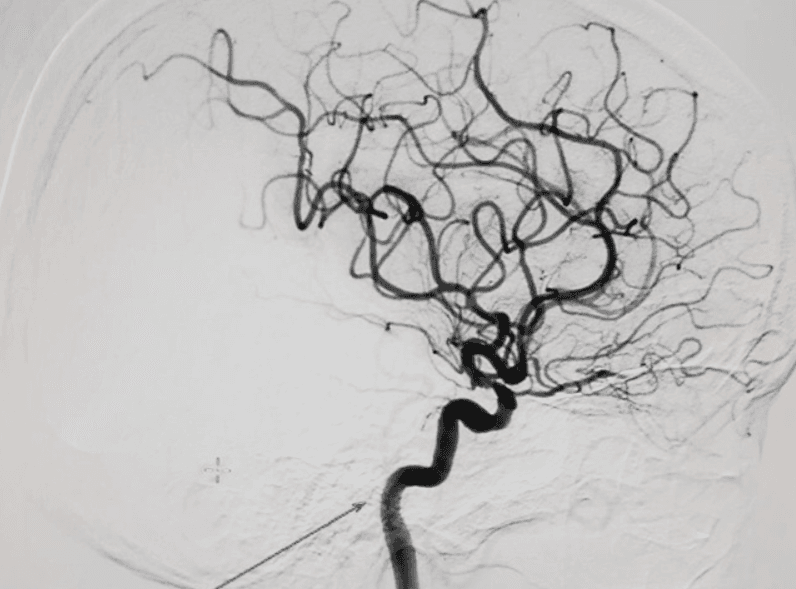

- Máy chụp mạch số hóa xóa nền (DSA);

Việc điều trị hẹp vị tràng dưới hướng dẫn của chụp mạch số hóa xóa nền được đánh giá là thành công khi:

- Về vị trí: Stent nằm đúng vị trí hẹp tắc vị tràng, đầu trên và đầu dưới bao phủ đoạn hẹp tắc ít nhất 1cm.

- Về chức năng: Khi bơm thuốc từ thượng lưu thấy có lưu thông xuống hạ

- lưu. Lòng ống tiêu hóa còn hẹp không nhiều hơn 30%

- Không có thoát thuốc đối quang ra ngoài đường tiêu hóa vào ổ bụng, hay khoang sau phúc mạc.

Tóm lại, kỹ thuật chụp mạch số hóa xóa nền (DSA) sẽ can thiệp điều trị từ trong lòng mạch máu, với ưu điểm xâm lấn tối thiểu mà không cần phải phẫu thuật mở. Một trong những ứng dụng phổ biến của phương pháp này là hướng dẫn nong và đặt stent ống tiêu hóa, giúp điều trị hẹp vị tràng không dùng thuốc, cũng như hạn chế biến chứng cho phẫu thuật.